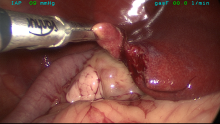

CT And Surgery Of Dog With Recurrent Abcess – Foreign Body

These are CT + intra-operative pictures of a dog who was referred to us with a recurrent abscess over ...